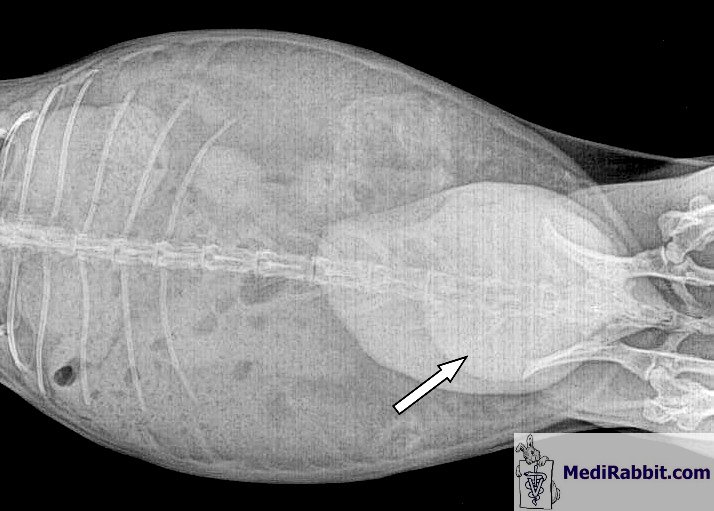

5 éve, és a szükséges öblítést rendszeresen végezték. Ezeket a röntgenfelvételeket a hólyag öblítése elött készítették és azt mutatják,

hogy a hólyag megtelt iszappal.